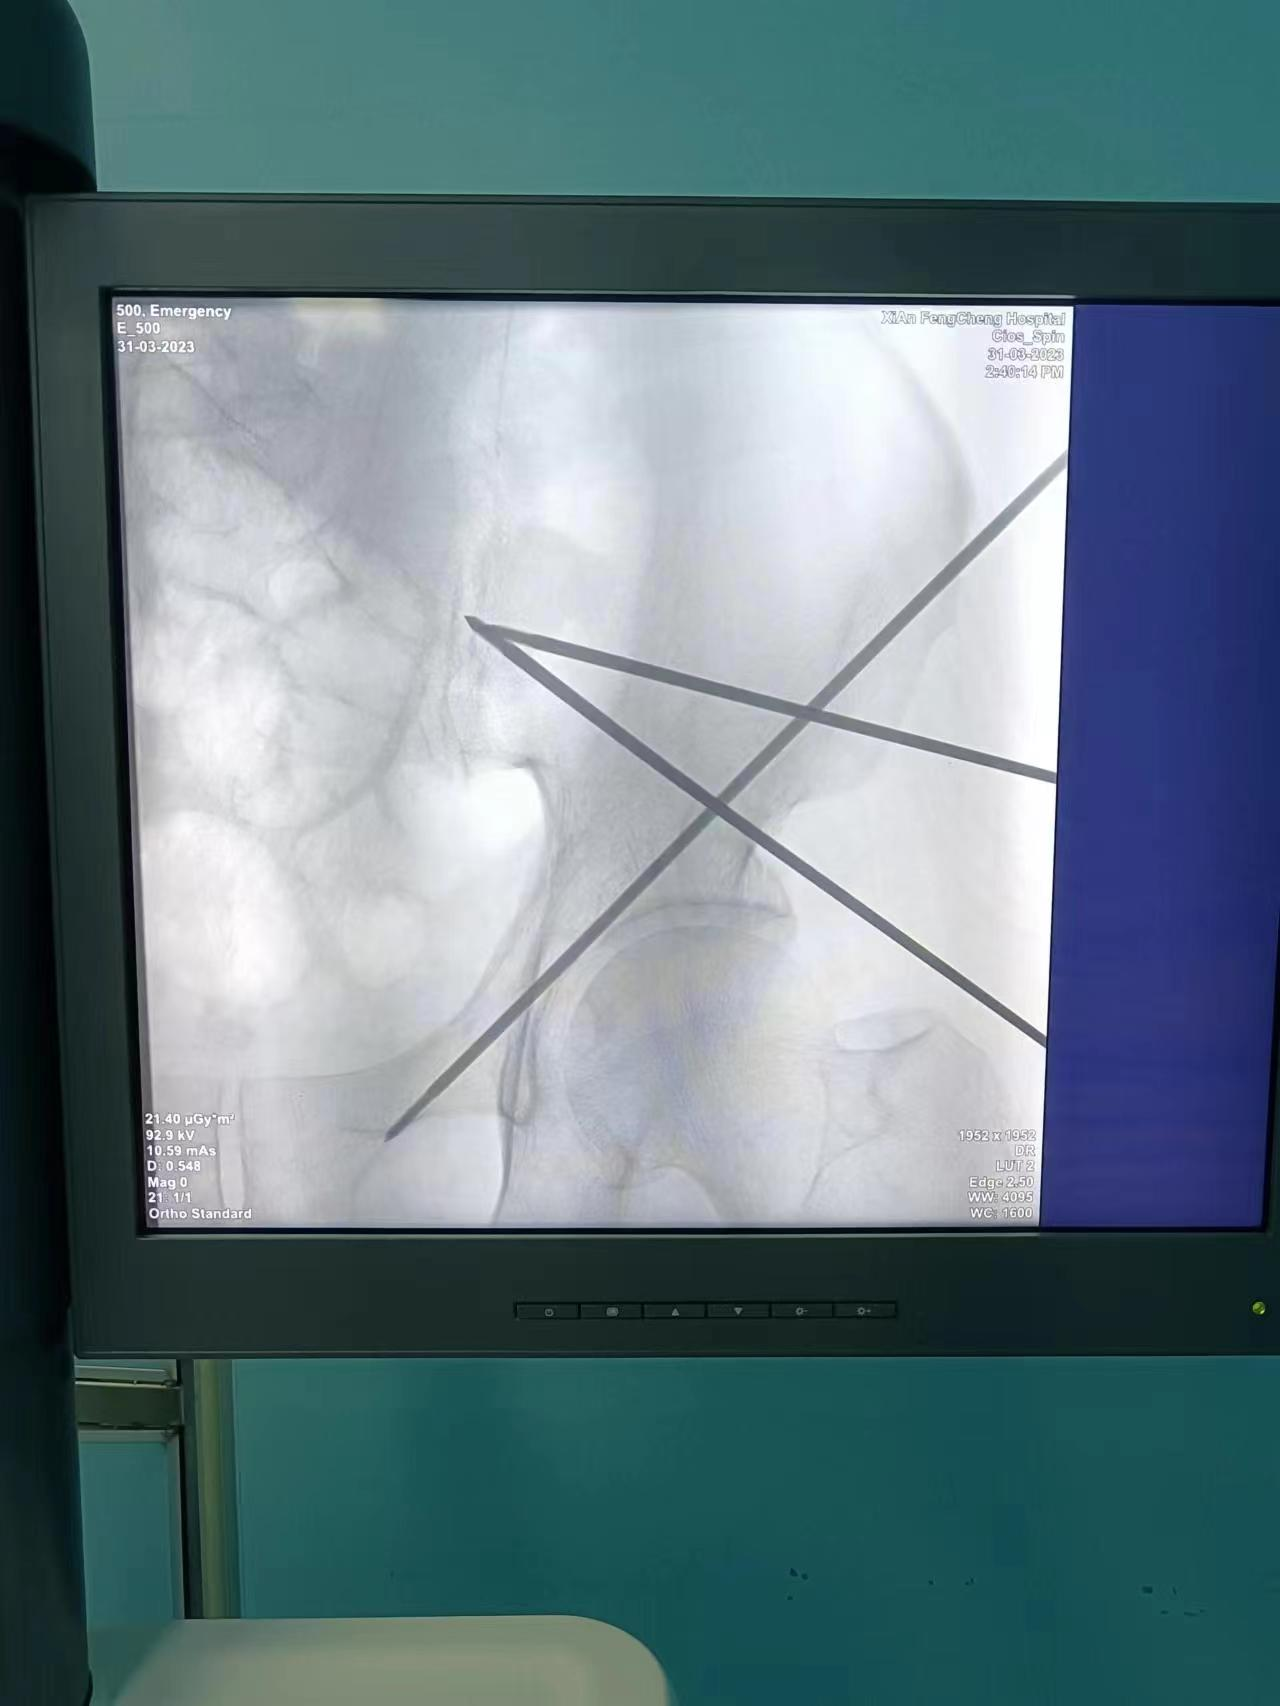

置钉前规划

骨科机器人定位、攻入导针